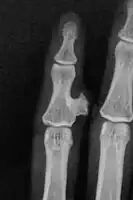

| Bizarre parosteal osteochondromatous proliferation, middle finger | |

Medical imaging usually shows a well-defined wide-based bony growth on the surface of bone.[5] It can be pedunculated and irregular, giving it a "bizarre" appearance, and is not connected to underlying bone.[2]

X-ray left foot: Bizarre parosteal osteochondromatous proliferation in 2nd toe